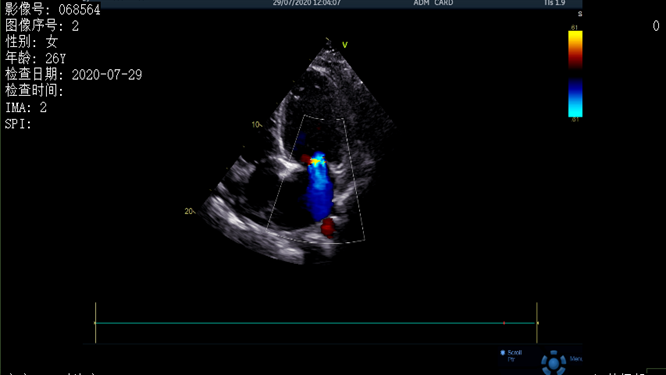

超聲結果顯示患者存在心包積液